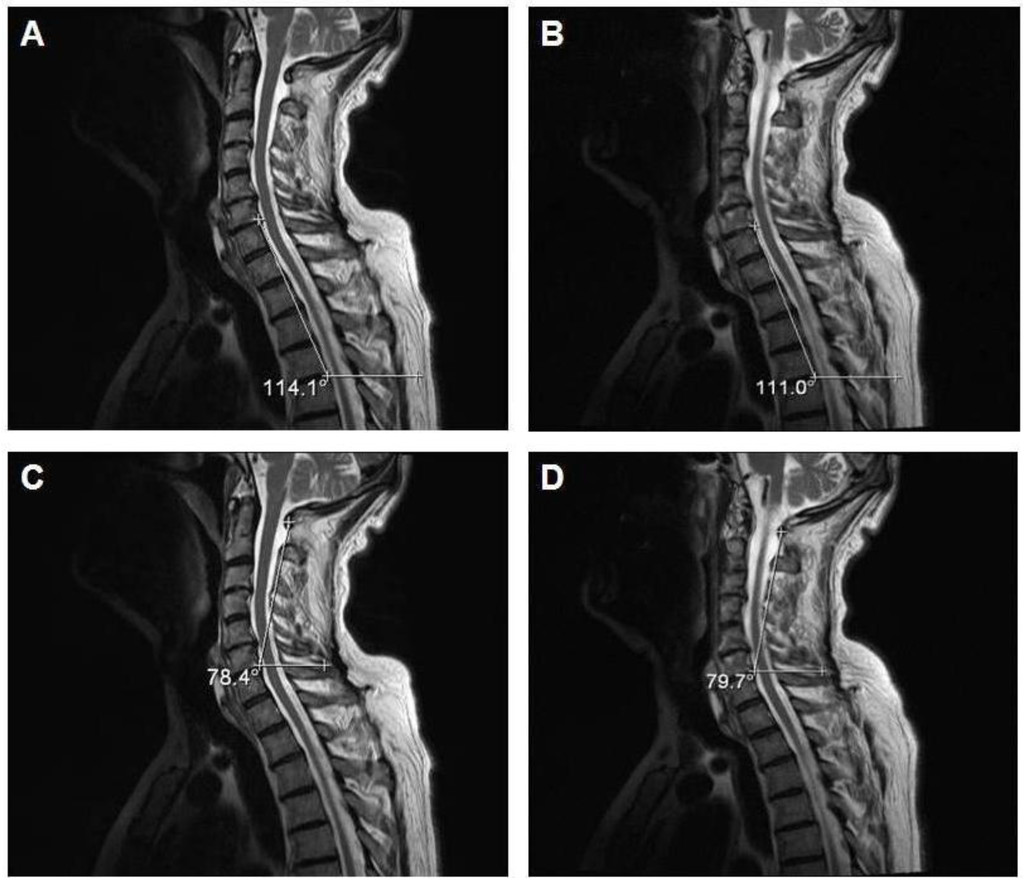

Figure 3 shows the MRI results of one of the three subjects (64 years) who was trained for 30 days with the Angel’s Wings. The figure shows the post-training variations in the curvatures of the cervico-dorsal (see Figure 3B) and cervical (see Figure 3D) column compared to those of the pre-training (see Figure 3A,C).

Figure 3.

Pre-exercise (A and C) and post-exercise (B and D) magnetic resonance imaging (MRI) images (sagittal T2 weighted fast spin echo images; TR/TE-4000/105) of one representative subject who performed the motor task daily (morning and evening) for a duration of 30 days.

In subjects who perform motor tasks daily (morning and evening) for 30 days, via MRI images, we demonstrated a realignment of the cervico-dorsal column between the pre- and post-training phases due to a variation of only a few degrees in its curvatures. Moreover, an improvement in posture is shown because, additionally, the gibbus, caused by a kyphotic posture, appears blunt. This data is important, considering the fact that the training period was 30 days, a relatively short period of time.